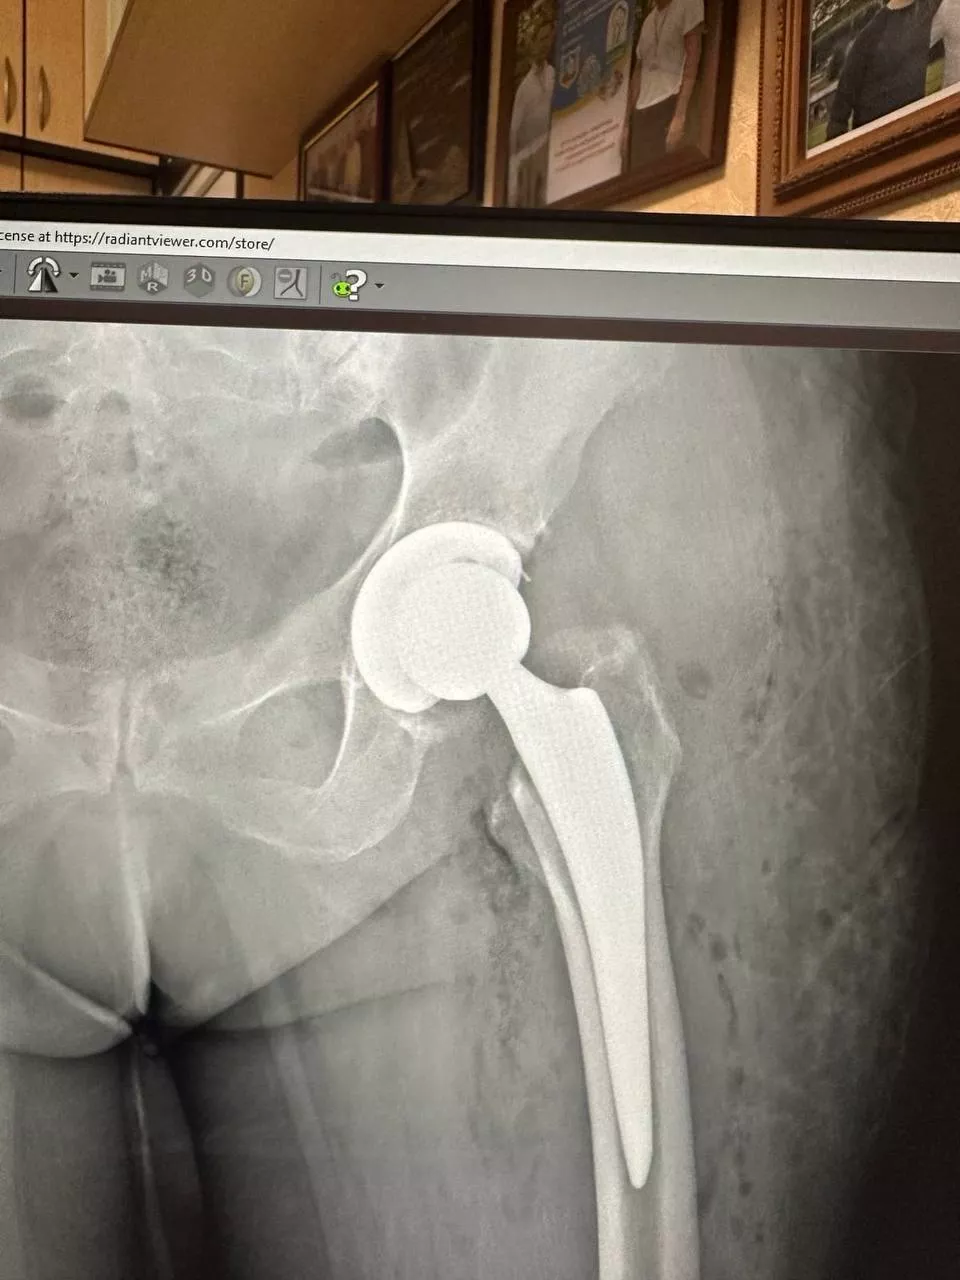

Ендопротезування кульшового суглоба

Заміна кульшового суглоба — одна з найефективніших операцій, яка вважається "золотим стандартом" в ортопедії. Цей вид хірургічного втручання виконується для лікування важких захворювань суглобів і відновлення їхньої рухливості. Під час операції пошкоджений суглоб замінюється на штучний імплантат, що дає змогу значно зменшити біль і повернути свободу рухів. Ендопротезування допомагає відновити повноцінне функціонування кульшового суглоба, забезпечуючи пацієнту активне і комфортне життя.

- Рентгенографія суглоба — дає змогу побачити структуру і стан кістки, оцінити ступінь пошкодження і виявити можливі деформації.